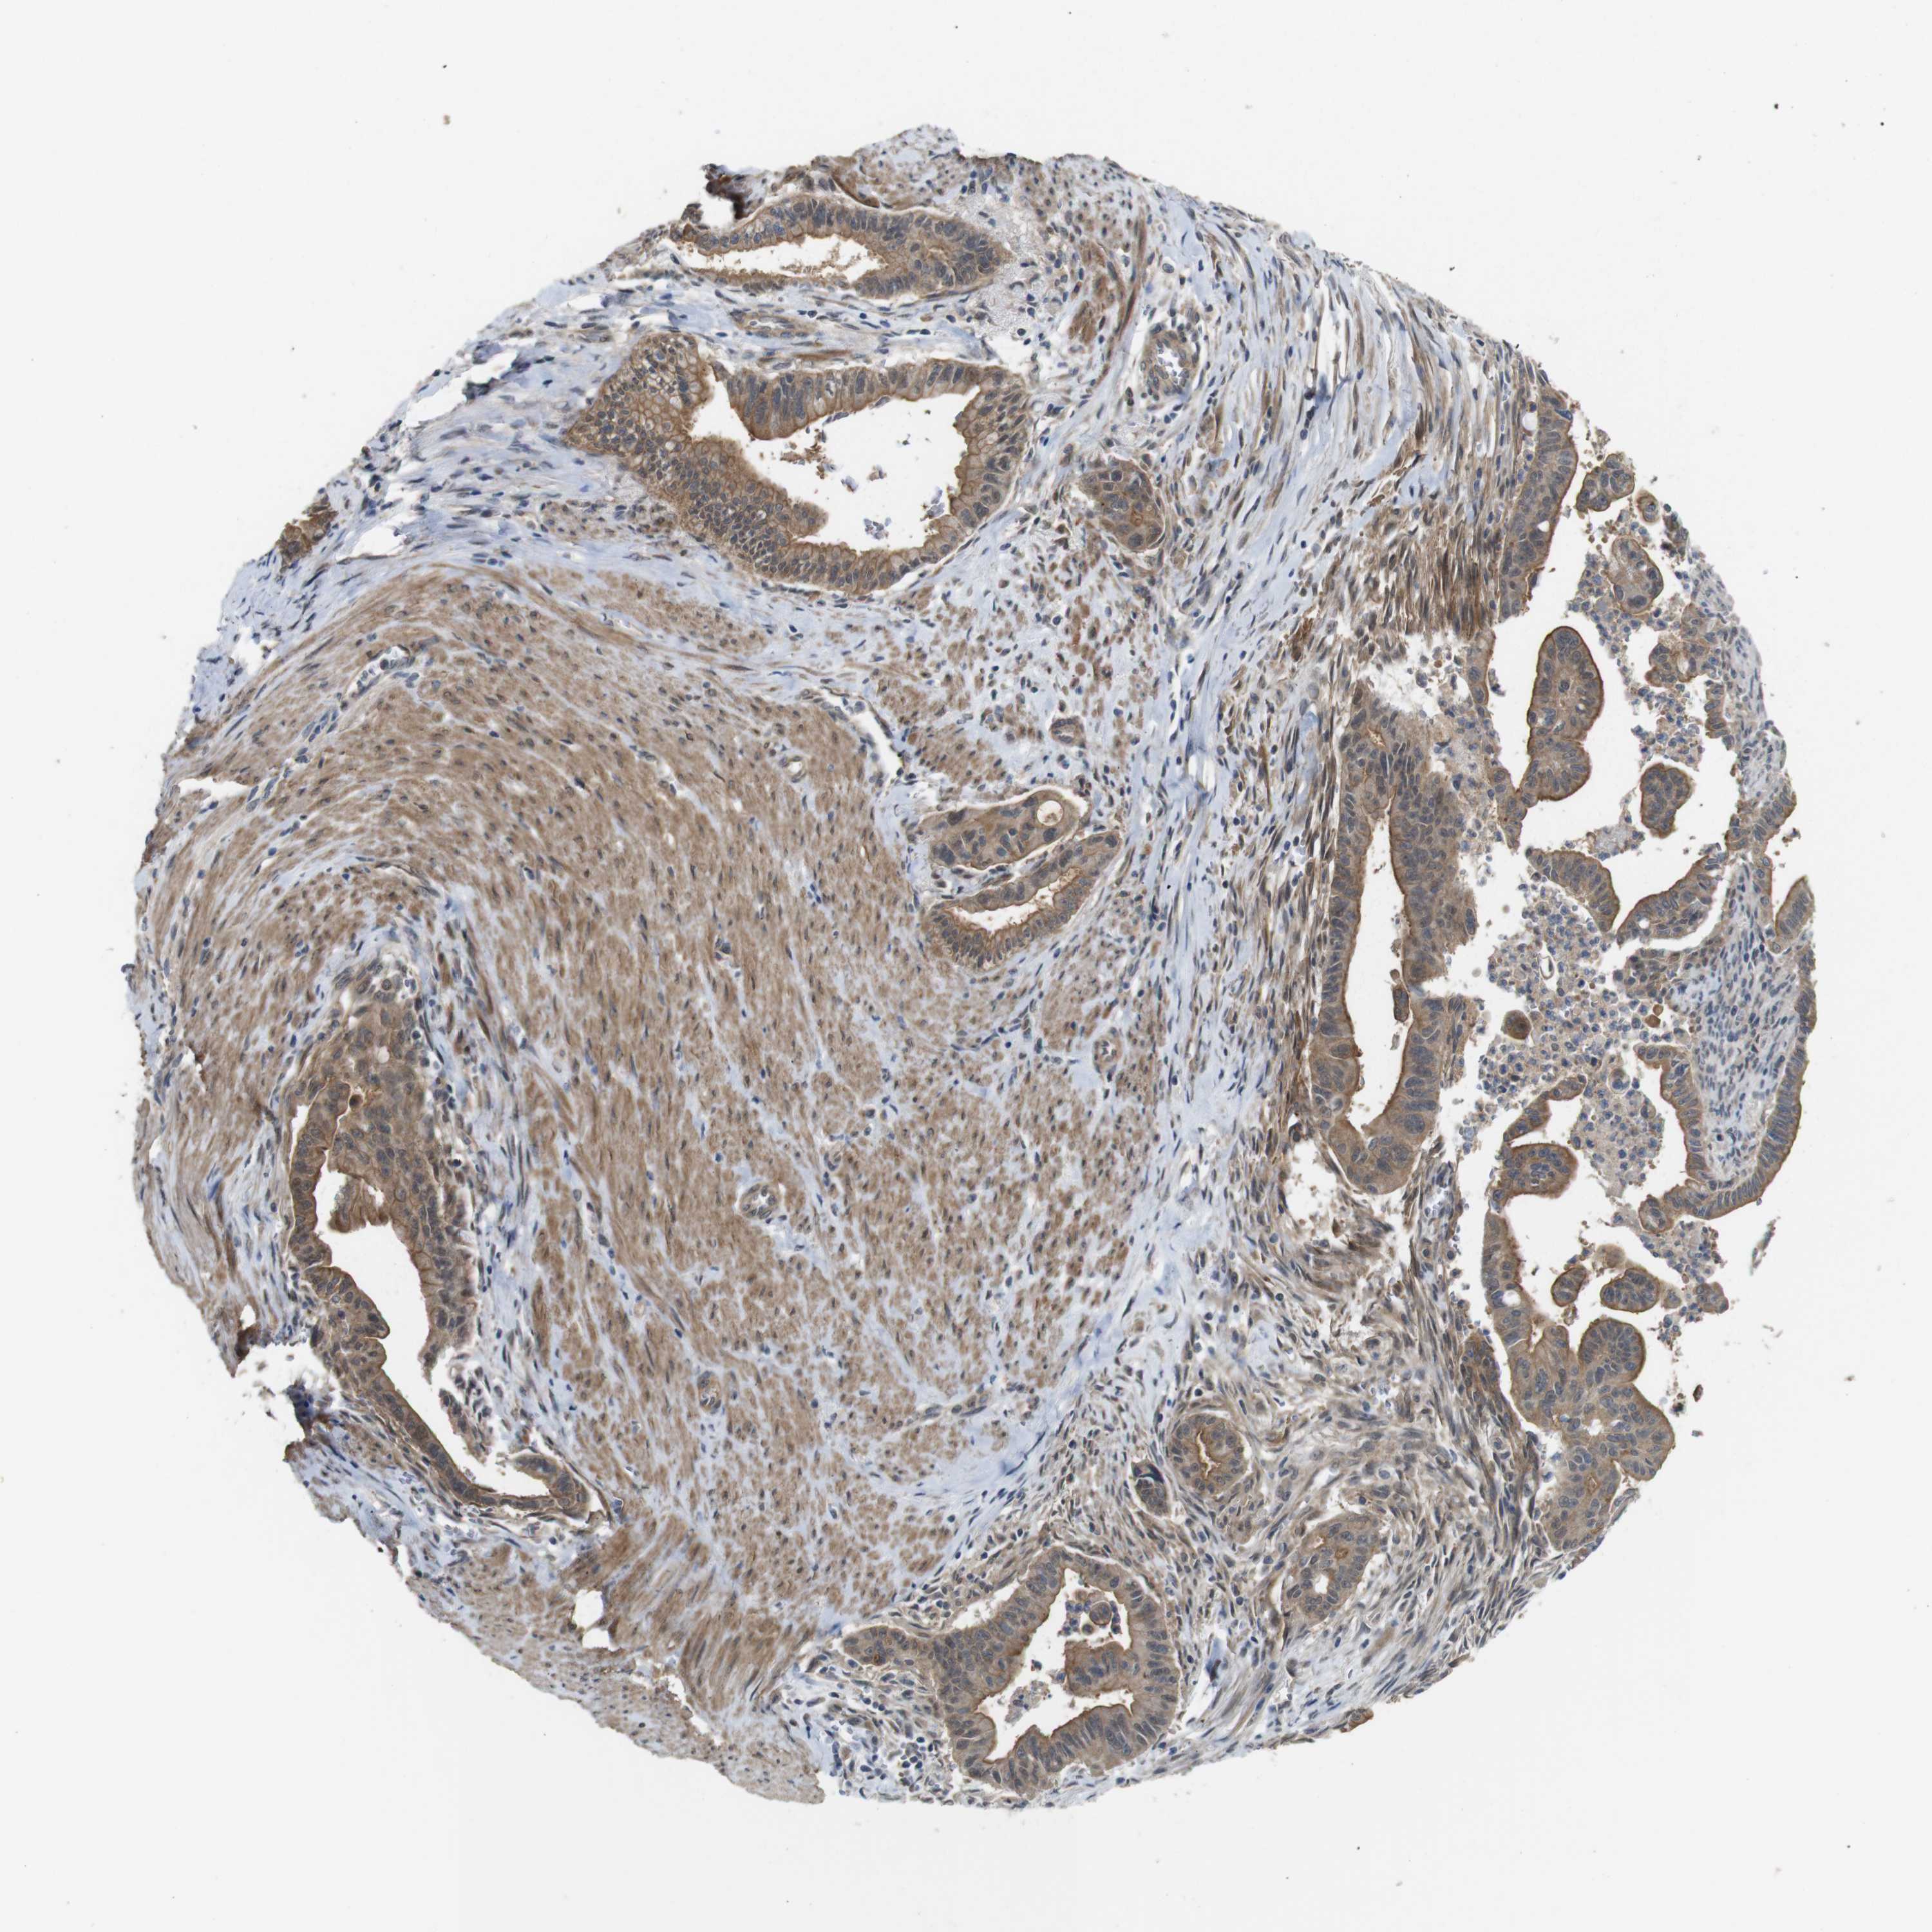

PANCREATIC CANCER - Protein expressioni

A mouse-over function shows sample information and annotation data. Click on an image to view it in a full screen mode. Samples can be filtered based on level of antibody staining by selecting one or several of the following categories: high, medium, low and not detected. The assay and annotation is described here.

Note that samples used for immunohistochemistry by the Human Protein Atlas do not correspond to samples in the TCGA dataset.

Antibody stainingi

Antibody staining in the annotated cell types in the current human tissue is reported as not detected, low, medium, or high, based on conventional immunohistochemistry profiling in selected tissues. This score is based on the combination of the staining intensity and fraction of stained cells.

Each image is clickable and will lead to virtual microscopy that enables deeper exploration of all samples and also displays staining intensity scores, fraction scores and subcellular localization as well as patient and tissue information for each sample.

Antibody HPA002382

Antibody CAB005109

Antibody CAB047311

Staining

High

Medium

Low

Not detected

Intensity

Strong

Moderate

Weak

Negative

Quantity

>75%

75%-25%

<25%

None

Location

Nuclear

Cytoplasmic/membranous

Cytoplasmic/membranous,nuclear

Adenocarcinoma, NOS

Adenocarcinoma, metastatic, NOS